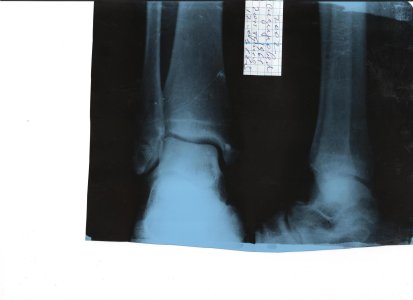

перелом малой берцовой кости со смешением

Здраствуйте, моей маме 51год 12 марта 2012г. она сломала ногу в травмопункте сделали снимок и поствавили диагноз перелом малой берцовой кости со смешение и наложили лангет от кончика большого пальца до середины икры с заходом по бокам на ступню (сверху ступни и нижней части икры впереди гипса нет), просим вас посматретить снимок и посоветовать нам когда можно ставать на ногу и через сколько дней снимать гипс.

ее лечащий врач сказал, что гипс нужно снимать через 50 дней и в течения этого периода нагрузку на ногу запретил, если бы Вы дали свой совет и посмотрели снимок, был бы премного благодарен.

Если смотреть только на снимок, то нагрузка возможна через 2 недели, а гипс до 4 недель. А ваш врач видел ногу и назначил правильное лечение.